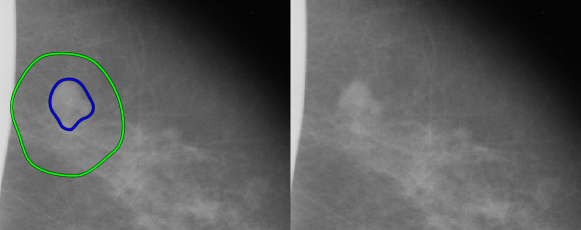

Similar to [7, 17, 6, 5], we use recall () at false positives per image (FPI) to compare the performance of our model with other studies (). Unlike in previous methods, we recall an object if it has IoU with ground true more than 0.1 since we have masks instead of bounding boxes and observe a relatively high proportion of true positives in diapason of . An example of such an object is shown in Fig. 3.